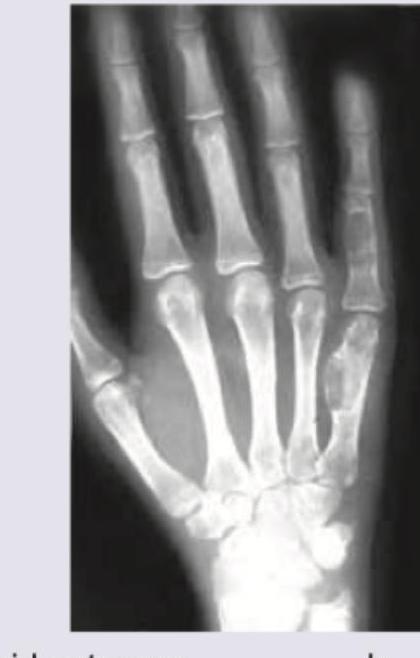

Spot the diagnosis based on the given X-ray of hand.

Explanation: ***Enchondroma*** - The X-ray image shows a **lucent, well-defined lesion** within the shaft of the 5th metacarpal bone, accompanied by some **cortical thinning** but largely preserved cortex. This appearance, particularly in the small bones of the hand, is classic for an enchondroma. - Enchondromas are benign cartilaginous tumors, often found incidentally, and their radiographic features include a **radiolucent geographic lesion** with occasional internal calcifications, though not clearly visible here. *Osteoid osteoma* - An osteoid osteoma typically presents as a small **lucid nidus less than 1.5 cm** surrounded by a prominent rim of **sclerotic bone**. - While it can occur in the hand, the lesion in the image is larger and lacks the characteristic central nidus with reactive sclerosis. *Simple bone cysts* - Simple bone cysts (also known as unicameral bone cysts) are typically **lucent, centrally located lesions** often found in the **metaphysis of long bones**. - They tend to be large and usually lack internal calcifications or the characteristic lobulated appearance seen in this lesion. *Chloroma* - A chloroma (also known as granulocytic sarcoma) is a solid tumor of **myeloid blasts**, typically associated with leukemia. - On X-ray, they usually present as **lytic bone lesions** that can cause bone destruction and soft tissue involvement, which is not consistent with the well-defined, lytic but contained lesion shown.